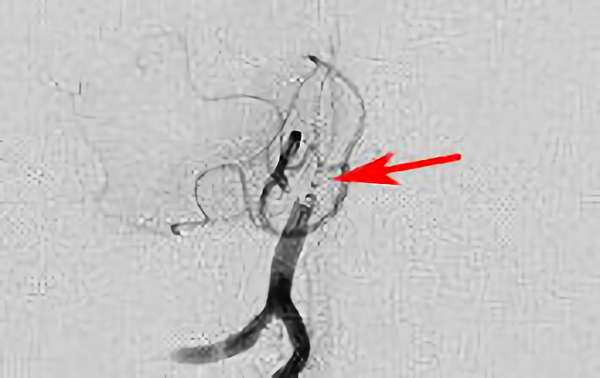

No.1631 手術前